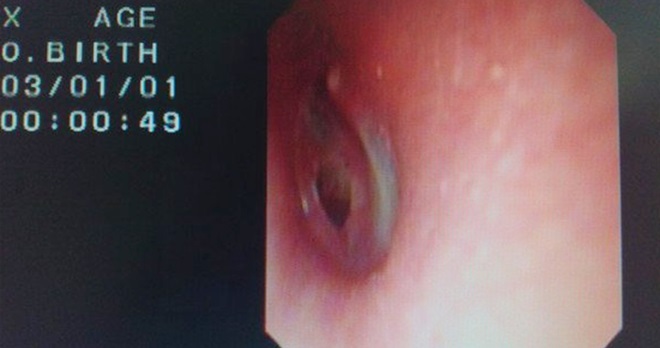

医师检查发现,男子外耳道有少量淤血,经清理后,在纤维耳镜下发现他右耳鼓膜有个小穿孔,周围充血并且伴耳鸣,有听力下降的状况。

所幸,男子没有神经损伤、没有感染,穿孔大约在一个月内可自行愈合,局部消毒清理后,无需特殊处理。

若2个月后鼓膜还未长好,可以择期进行鼓膜修补术。医师刘刚也提醒,年轻情侣以亲吻来表达爱意时,一定要注意不能用力亲吻耳孔部位,避免形成负压而致鼓膜穿孔。